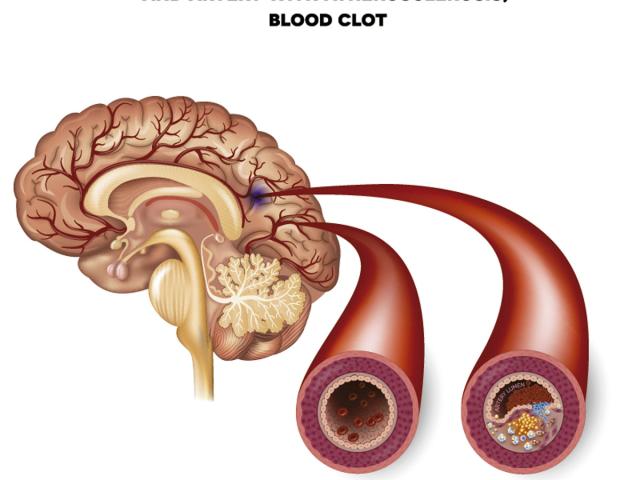

La hipertensión es una condición médica que aumenta el riesgo de padecer enfermedades cardíacas, cerebrales y renales.